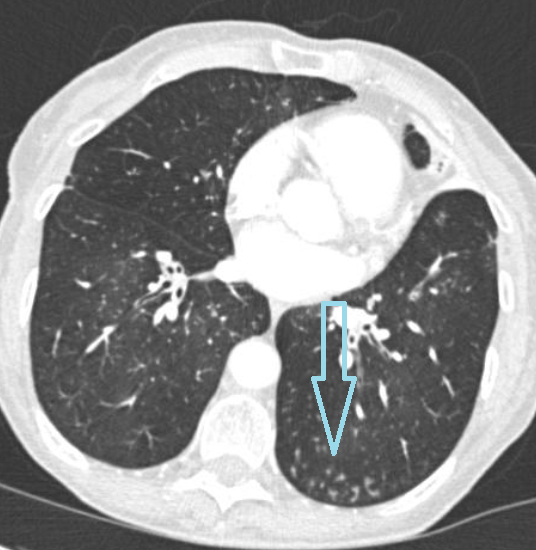

- по типу «матового стекла» - уже не такие плотные, и как будто мы видим мутноватое затуманенное стекло, через которое врачу видно остальную ткань легкого;

- частично солидные – как Вы догадались, такой очаг имеет черты и солидного и по типу «матового стекла».